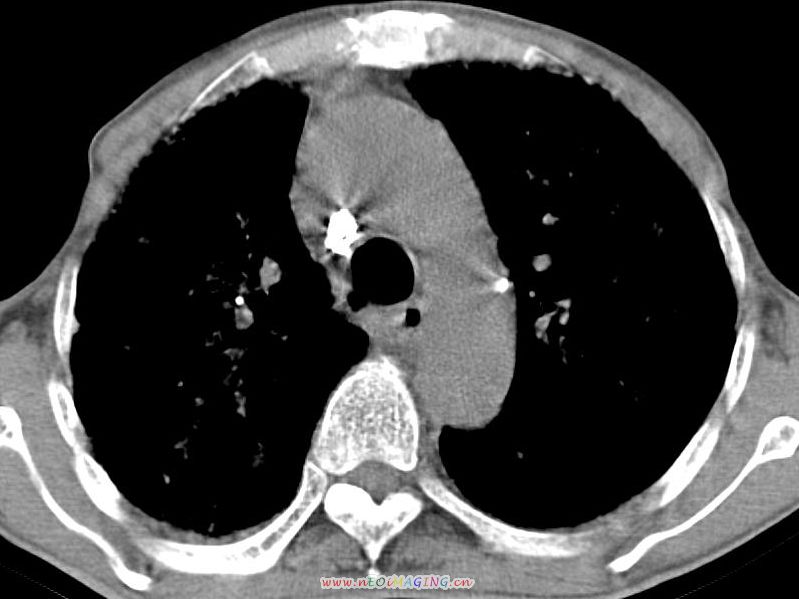

患者咳嗽月余,高热数天,咳黄色稍脓痰。

双肺野分布多个小结节状高密度影,其内散在斑片状模糊影,气管。支气管通畅,纵隔内淋巴结钙化,胸膜局限性增厚粘连,胸腔少量积液。结合病史考虑结核并感染的可能性大,胸膜炎并积液。肺泡癌待排。

纵隔内见钙化的淋巴节,上肺见钙化灶,双肺均匀弥漫分布小结节影,边缘较清楚,能不能考虑是在矽肺的基础上并发的结核和感染,请详细了解病史结合临床.